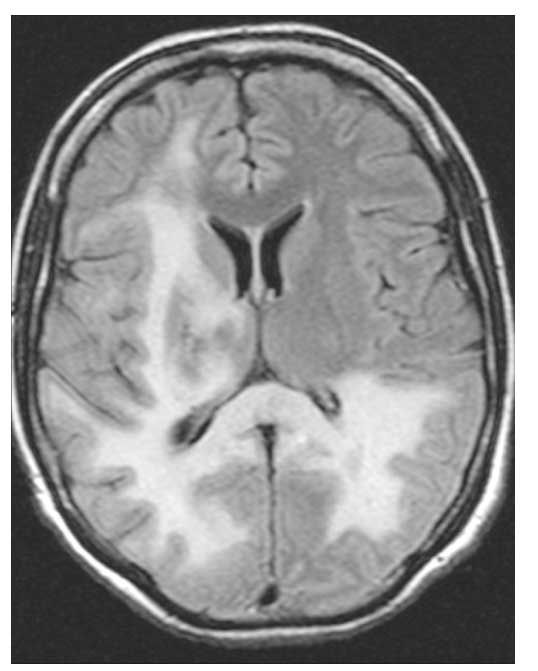

An antiretroviral regimen of tenofovir, emtricitabine, and lopinavir/ritonavir was started. Within 4 weeks, the patient's HIV-1 RNA level declined to less than 75 copies/mL. However, her CD4 count did not improve over a 2-month period. Clinical deterioration was heralded by worsening left-sided weakness and the sudden development of blindness. Serial brain MRI scans obtained over a 45-day period showed extensive progression of the lesions that accompanied the neurological changes (Figures 2 and 3). Immune reconstitution inflammatory syndrome (IRIS) was considered, although many diagnostic features were not present; however, neurological deterioration prohibited additional brain biopsies. Nevertheless, glucocorticoid treatment was initiated but without success. The patient experienced progressive weakness and died of respiratory failure 3 months after her initial MRI.

Figure 3. Brain MRI scan obtained 2 months after initial MRI demonstrates involvement of frontal lobe, thalamus, and near-complete bilateral occipital involvement. Not shown here is the vertical spread of pons, midbrain, and cerebellum that was present.

Diagnosis of PML is based on clinical findings, neuroradiographic imaging, and virological testing. Fifty-three percent of patients with PML present with hemiparesis, and 43% present with cognitive impairment. Other, less frequent presentations include speech or visual deficits, ataxia, and seizures.4 Classic MRI findings are well-demarcated, asymmetric lesions in periventricular and subcortical white matter. The lesions are characteristically hyperintense on FLAIR/T2-weighted images, hypointense on T1-weighted images, and non-enhancing with gadolinium and do not create mass effect.4 JCV DNA can often be isolated from CSF by PCR. However, early use of antiretroviral therapy may allow rapid CSF clearance, and the sensitivity of CSF PCR in some studies is estimated to be as low as 53%.3 Brain biopsy is the gold standard for diagnosis of PML, with tissue samples showing JCV infection of oligodendrocytes, associated demyelination, and reactive changes.3